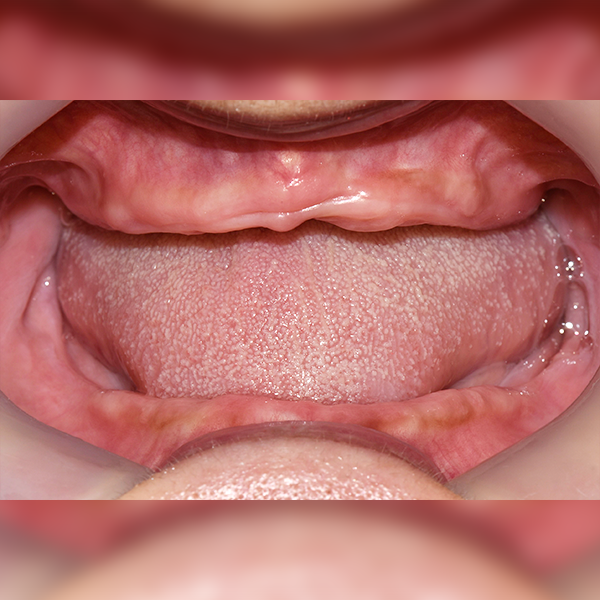

3. Trường hợp 15. Ông Kim * Ân, 60 tuổi 2018-08-02 / 2019-05-30

Trường hợp 15. Ông Kim * Ân, 60 tuổi 2018-08-02 / 2019-05-30

Before Before

After After